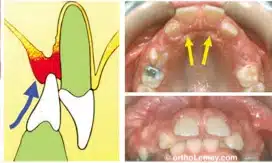

Gingival Loss (Related with Deep Bite)

در دیپ بایت های عمیق و کامل احتمال صدمه به بافت نرم وجود دارد. چنانچه بهداشت بیمار ضعیف باشد و یا تروما به لثه پالاتال وارد شود، التهاب ایجاد می شود. این التهاب با ترومای ناشی از بایت بر لثه پالاتال تشدید می شود و می تواند منجر به تورم، صدمات اسپیرال و از دست رفتن دائمی لثه شود.